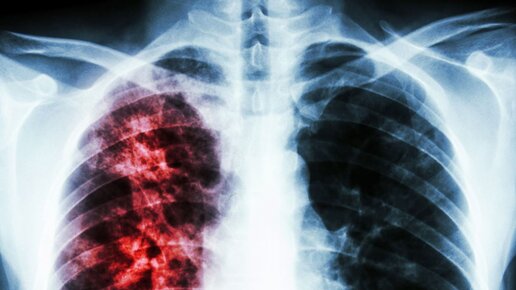

Как определить туберкулез на ранней стадии

В 2021 году Россия достигла исторического минимума по смертности от туберкулеза. По данным "Национального медицинского исследовательского центра фтизиопульмонологии и инфекционных заболеваний" за 20 лет заболеваемость снизилась более чем в три раза, а смертность — более чем в четыре раза. Тем не менее инфекционное заболевание до сих пор представляет опасность, особенно в свете коронавирусной пандемии. "Рамблер" рассказывает, как определить болезнь на ранней стадии. О ранних признаках туберкулеза пишет Елена Валерьевна Зырянова, врач-фтизиатр высшей категории...